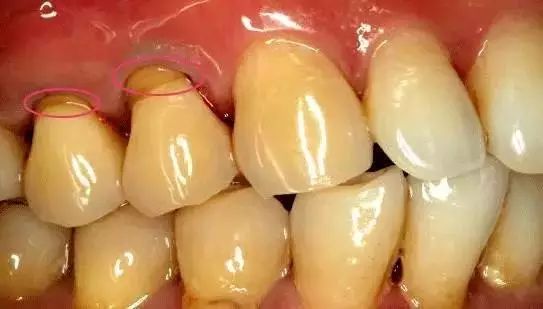

牙周炎示意圖